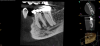

The quality of the initial NSRCT is inversely associated with RETX outcomes, with poorer quality initial treatment tied to more predictable retreatment (Figure 6 through Figure 8).23 Inadequate quality of the initial NSRCT (eg, untreated anatomy, under-instrumentation, ledged and underfilled canals, and overextended obturation) was associated with greater predictability following RETX. However, if clinicians cannot identify and correct the mistakes made in the previous root canal therapy, it becomes more challenging to improve treatment outcomes.23

Fig 6. Identifiable inadequate NSRCT is associated with predictable RETX. Fig 6: Preoperative periapical radiograph showing AP, tooth No. 20. Fig 7. Postoperative periapical radiograph. Fig 8. Six-month follow-up periapical radiograph showing a significant decrease in size of the AP.

Figure 6

Fig 7. Identifiable inadequate NSRCT is associated with predictable RETX. Fig 6: Preoperative periapical radiograph showing AP, tooth No. 20. Fig 7. Postoperative periapical radiograph. Fig 8. Six-month follow-up periapical radiograph showing a significant decrease in size of the AP.

Figure 7

Fig 8. Identifiable inadequate NSRCT is associated with predictable RETX. Fig 6: Preoperative periapical radiograph showing AP, tooth No. 20. Fig 7. Postoperative periapical radiograph. Fig 8. Six-month follow-up periapical radiograph showing a significant decrease in size of the AP.

Figure 8